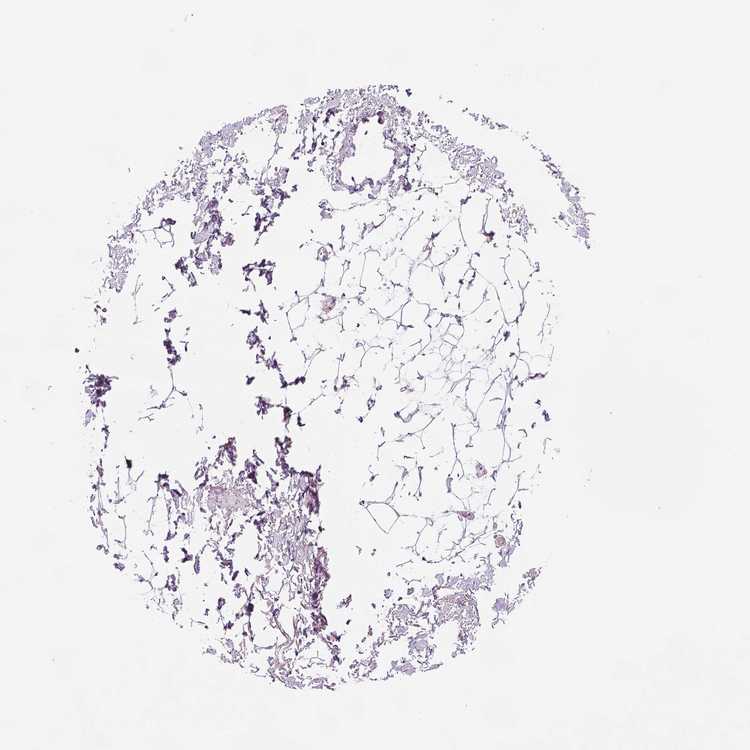

SOFT TISSUE 2 - Antibody stainingi

Antibody staining in the annotated cell types in the current human tissue is reported as not detected, low, medium, or high, based on conventional immunohistochemistry profiling in selected tissues. This score is based on the combination of the staining intensity and fraction of stained cells.

Each image is clickable and will lead to virtual microscopy that enables deeper exploration of all samples and also displays staining intensity scores, fraction scores and subcellular localization as well as patient and tissue information for each sample.

Antibody HPA018897Antibody HPA074629

Fibroblasts Not detectedNot detected

Peripheral nerve Not detectedNot detected